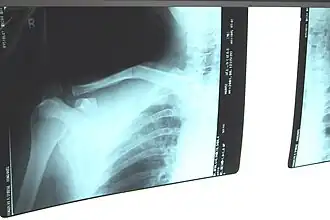

| Raio-X de uma fratura de clavícula direita. | |

Uma fratura de clavícula é uma fratura óssea na clavícula.